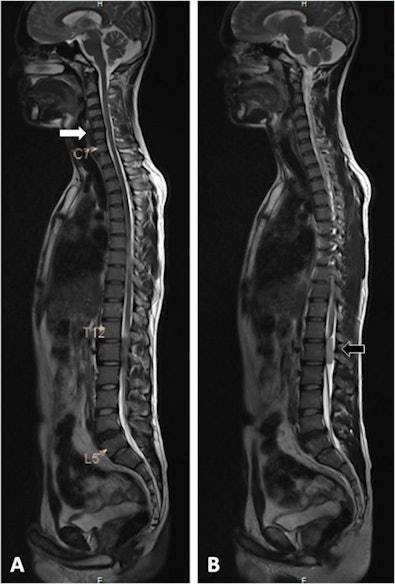

The group aimed to show how detailed images of the spinal column and adjacent spinal regions and paravertebral organ systems can reveal asymptomatic yet significant incidental findings.

In group A, 84 patients had incidental findings in the vertebral column and 38 patients had incidental findings in the spinal cord. Incidental findings within the spine included vertebral hemangioma (n = 60, 4.5%), diffuse vertebral marrow changes (n = 18, 1.2%), vertebral metastasis (n = 2), incidental cord myelopathy (n = 21), intradural tumor (n = 7), and others. A total of 33 patients required surgical intervention for their incidental findings (2.2%).

In group B, pelvic incidental findings were most prevalent (n = 79, 5.3%) followed by retroperitoneal abdominal findings in 22 (1.48%), and intracranial incidental findings in 9 (0.60%). A total of 32 (2.1%) of these pathologies required further specialist medical or surgical evaluation.